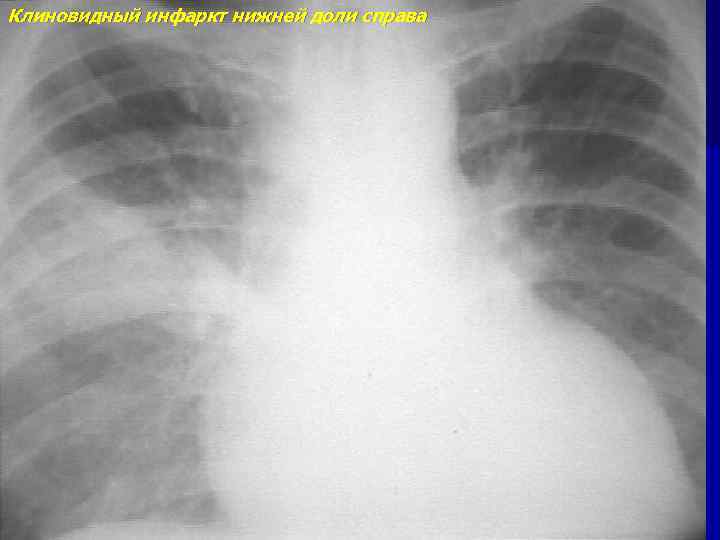

Клиновидный инфаркт нижней доли справа

Клиновидный инфаркт нижней доли справа - динамика через месяц